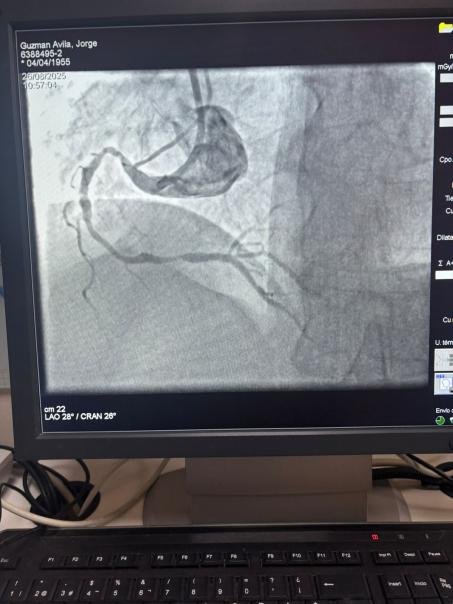

Мы гордимся тем, что поделились замечательным случаем из больницы Sótero del Río, Чили, где доктор Мартин Вальдебенито успешно вылечил сильно кальцинированное поражение в правой коронарной артерии (первая кривая), используя нашу систему катетера с расширенным баллоном IVL.

Процедура достигла выдающихся результатов, при этом кальцинированная область эффективно треснулась и поток сосудов восстановился. Это является еще одной вехой в расширении глобального доступа к передовым решениям для сложной коронарной кальцификации.

Сравнение между предварительными и послепроцедурными ангиографическими изображениями ясно демонстрирует значительное клиническое влияние нашей технологии IVL.